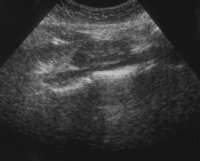

Bei einer jugendlichen Patientin kam es in Folge eines aberrierenden Gefäßes zum Harnstau im linksseitigen Hufeisennierenanteil mit Ausbildung eines fieberhaften Harnwegsinfektes. Unter der Diagnose eines aszendierenden, fieberhaften Harnwegsinfektes wurde die Patientin stationär aufgenommen, nach antibiotischer Therapie, parenteraler Flüssigkeitsapplikation und Bettruhe entfieberte die Patientin. Die Diagnostik ergab in der Sonographie einen Harnstau im linken Nierenanteil mit Verdacht auf Hufeisenniere (Abbildung 4).